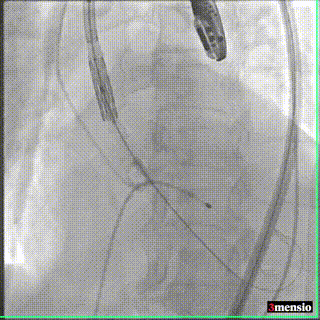

2021年12月17日,四川省人民医院结构性心脏病团队成功挑战高龄主动脉瓣严重狭窄合并弥漫钙化,顺利完成SAPIEN 3瓣膜植入。在团队成员紧密配合下,克服患者入路狭小弥漫钙化病变,充分利用SAPIEN 3瓣膜的优异性能,顺畅完成过弓、跨瓣及释放操作,手术取得圆满成功。这也是四川省人民医院首例应用SAPIEN 3瓣膜完成的TAVR手术。